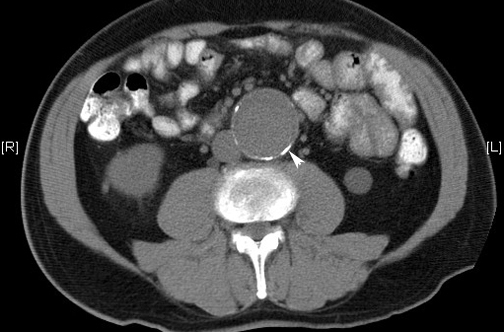

Aneurismas de aorta abdominal: más cirugías y menos mortalidad en EEUU

29 noviembre 2016

La tasa de cirugías para reparación electiva del aneurisma abdominal en EEUU duplica la de Inglaterra, pero la mortalidad por rotura aneurismática es tres veces menor. New England Journal of Medicine, 24 de noviembre de 2016